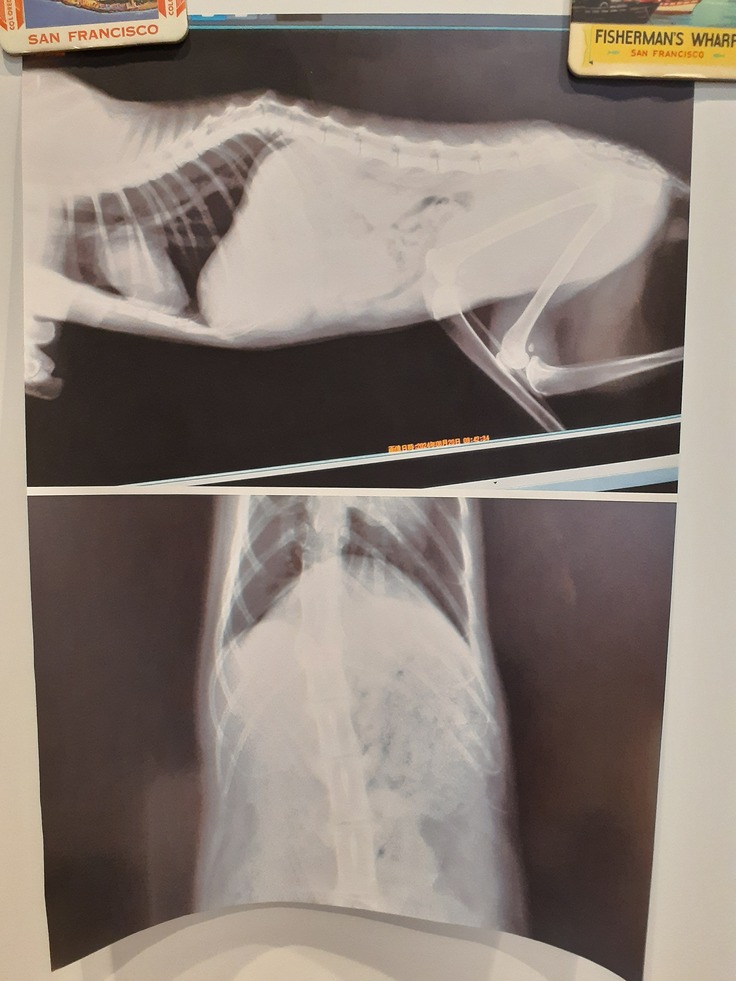

そして【そあら君】

22日夜遅くに驚くほどの血尿がありました。

エコー、尿検査をして、膀胱が汚れていること、ちょっと詰まってしまったこと、雑菌が繁殖していることが分かりました。

以下【そあら君】のファイルです。